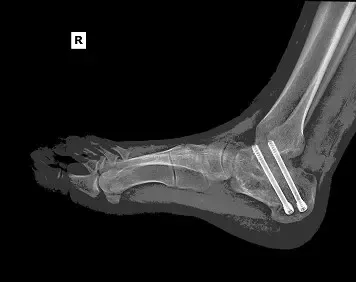

A middle-aged male construction worker presented with persistent right ankle pain and instability following a work-related injury. The patient sustained a right calcaneus fracture after jumping from a collapsing trailer while unloading materials. His injury occurred while working as an ironworker, and he required open reduction and internal fixation (ORIF) of the right heel at a tertiary medical center.

The patient underwent right subtalar arthrodesis with hardware removal at a local medical center. Intraoperatively, significant post-traumatic changes, joint degeneration, and residual deformity were observed. A structural bone graft was placed, and internal fixation was used to achieve stability. The procedure was successfully completed with minimal blood loss.

Follow-up X-rays: Confirmed hardware in situ with robust fusion progression.

By week 6 post-op, he was transitioned out of the boot and continued progressive loading of the ankle joint.

By the final follow-up, he was fully weight-bearing, ambulating independently, and had resumed daily activities. Although mild residual stiffness and swelling persisted, he reported no limitations in basic mobility.